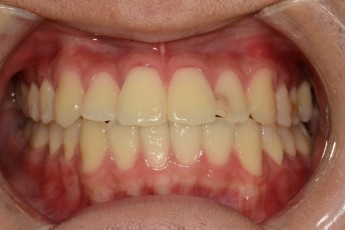

Before

After